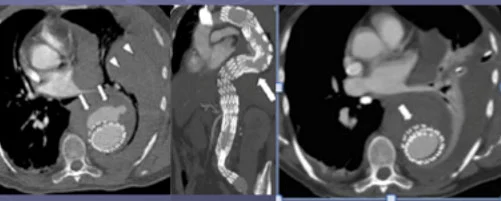

Embolizzazione percutanea per trattamento endoleak sotto guida radiologica